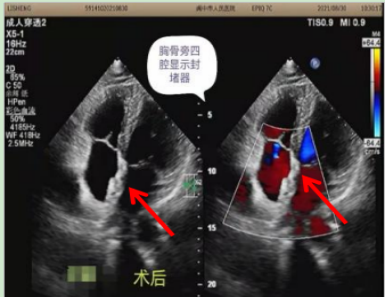

术前超声心动图

术后超声心动图